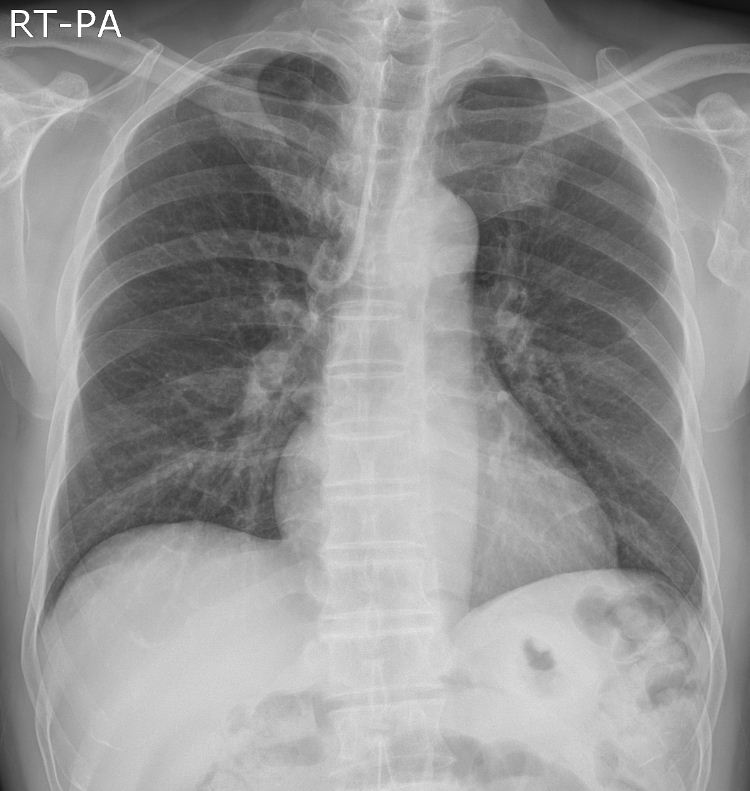

¿Ü·¡Áø·áº¼ ¿¹Á¤ÀÎ CXRÀÔ´Ï´Ù. ÀÌ»óÇÑ Á¡ Çѹø ºÁº¸¼¼¿ä ^^

CTÂïÀ» ¿¹Á¤Àε¥ ÂïÀ¸¸é °á°ú ¿Ã¸±²²¿ä

Chest CT ¿Ã·Á ÁÖ¼¼¿ä